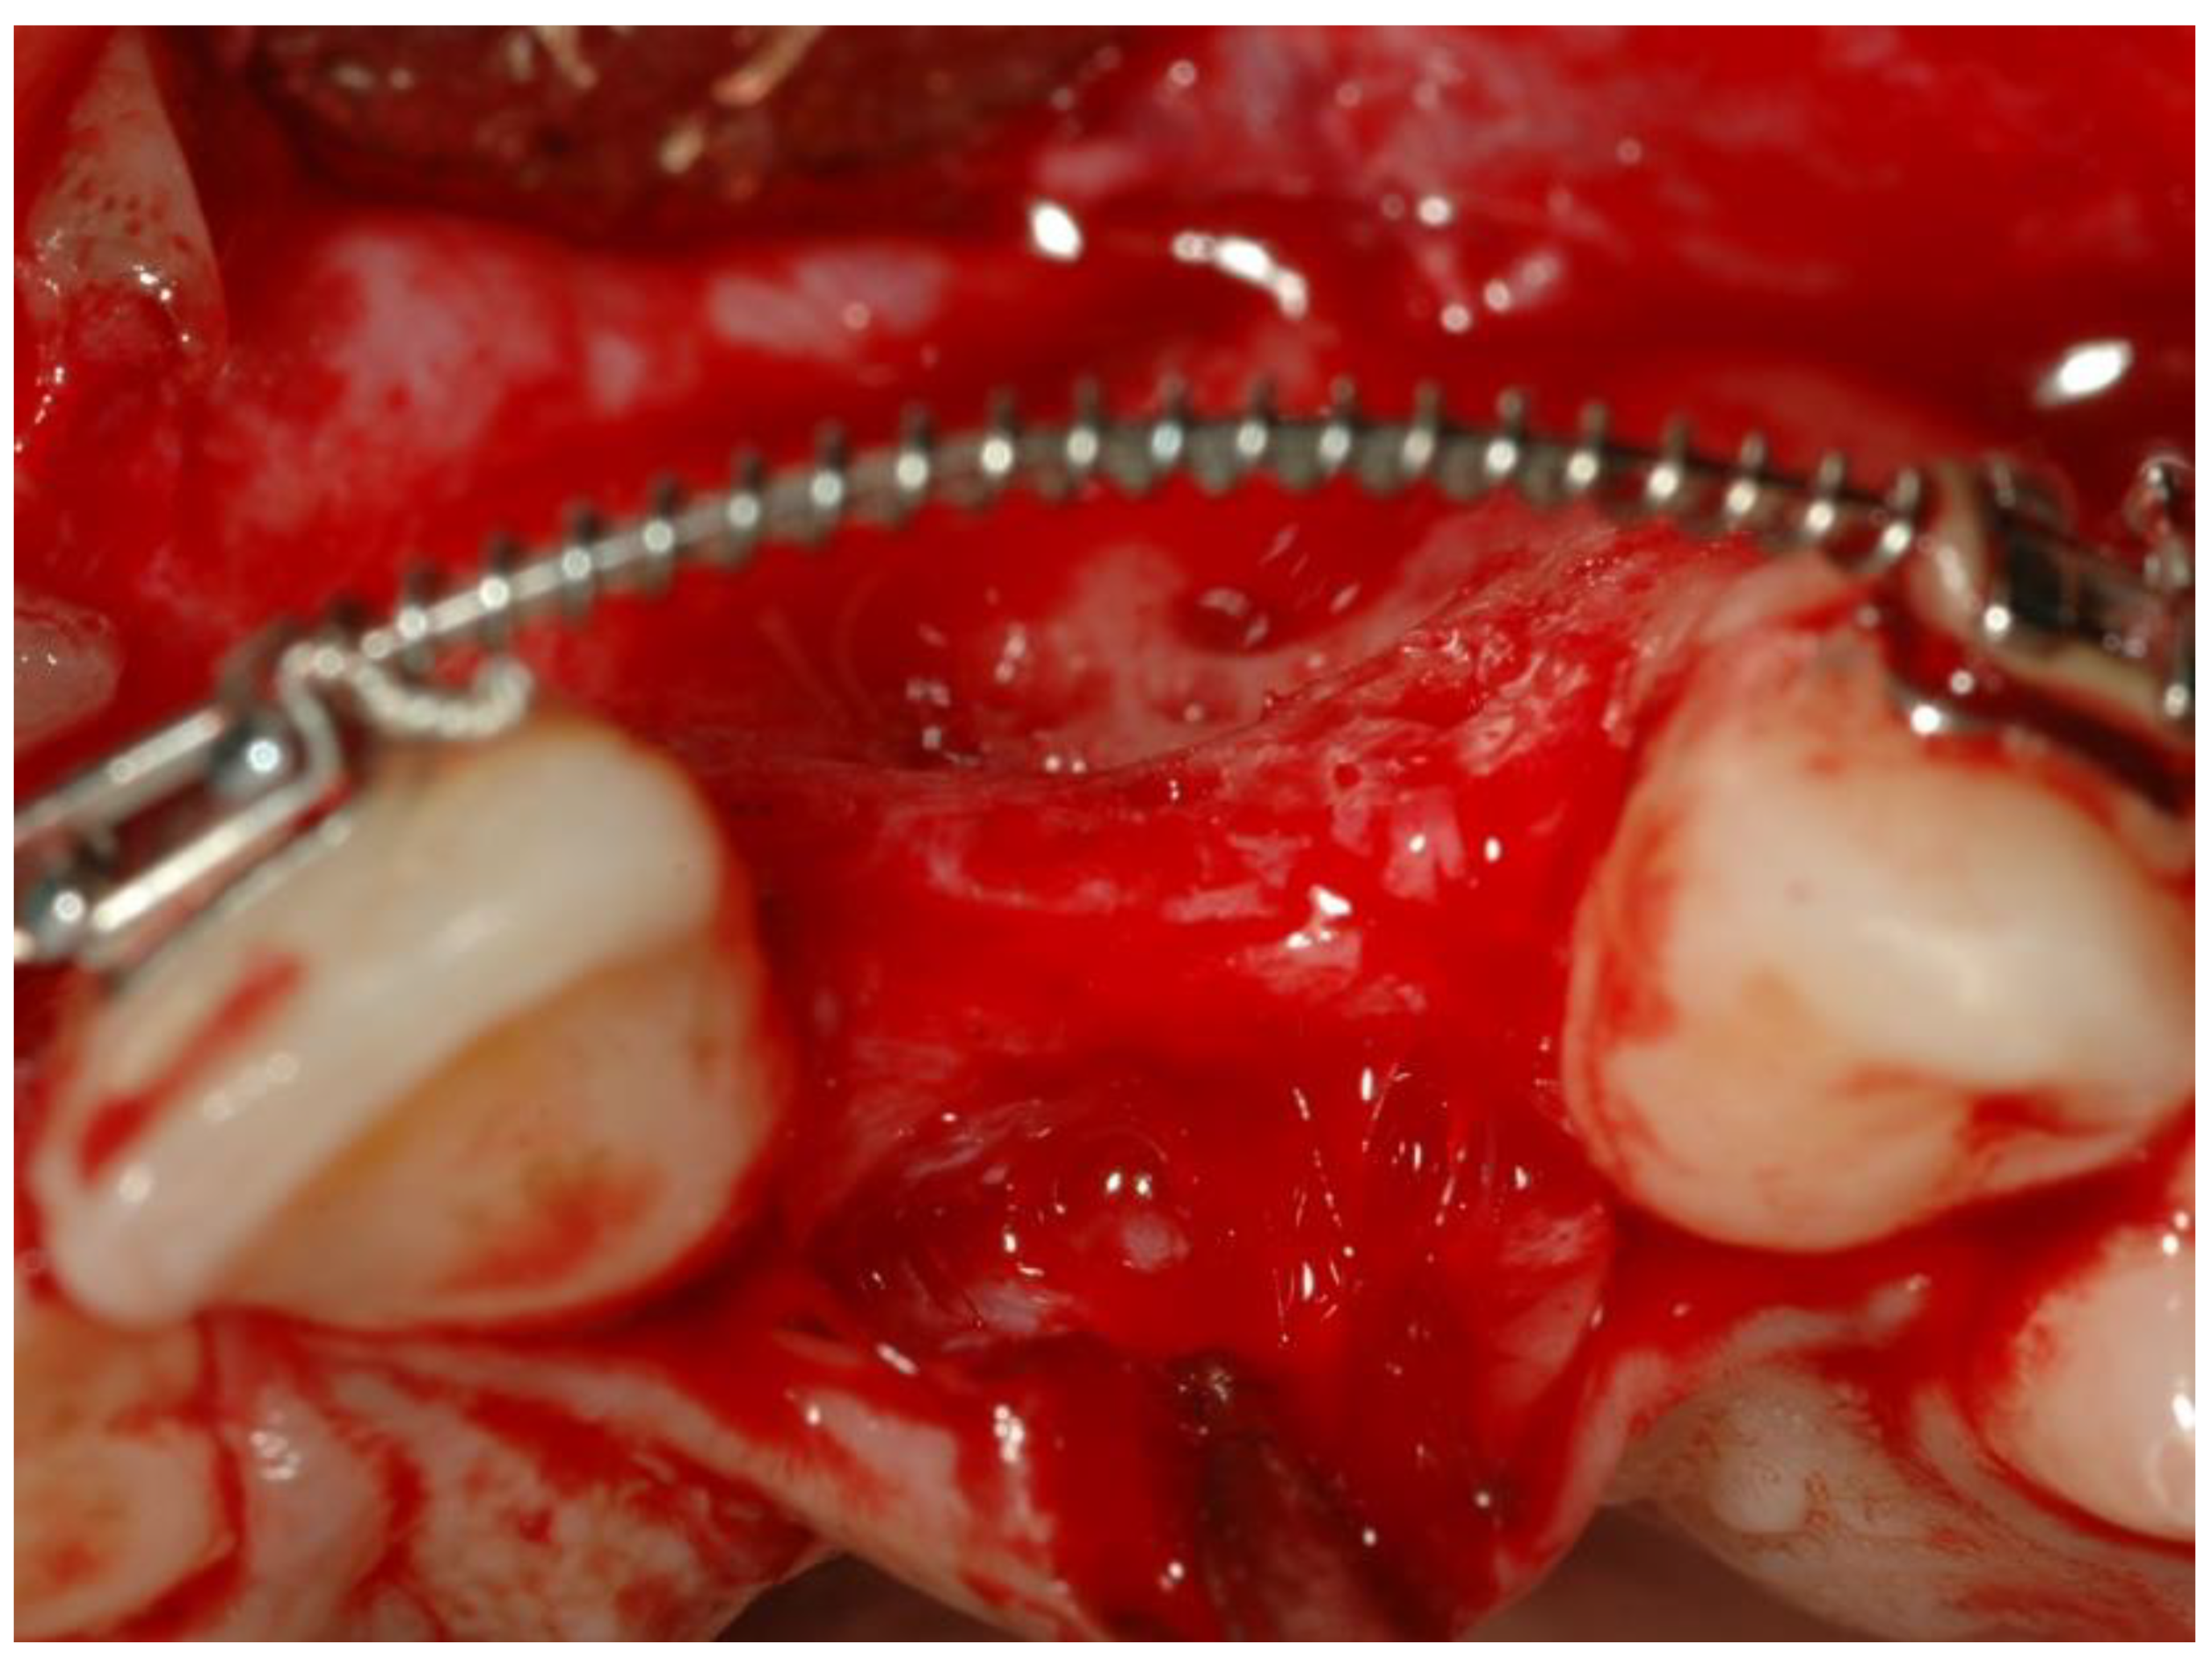

- Bone augmentations using cancellous allogeneic bone-blocks.

- Six months later, implant insertion followed immediately by a temporary restoration placement.